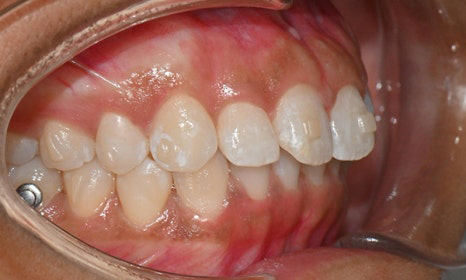

장치 착용 2달 후 사진 (2025.6)

교정을 시작하고 두 달 뒤,

8번째 장치를 착용하고 있을 때 찍은 사진을 보면

치아 배열도 많이 좋아졌고, 공간도 거의 닫혔어요.